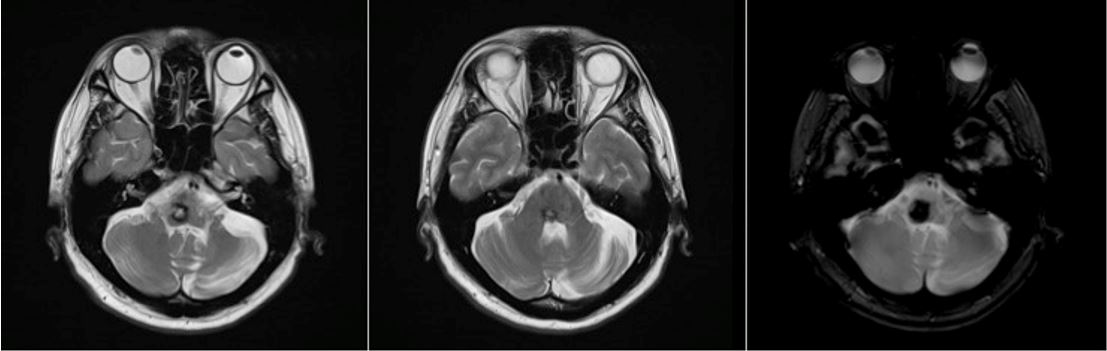

On magnetic resonance imaging, there is a hemorrhage with a complete hemosiderin ring at the level of the pons/ponto-medullary junction, associated with a well-defined lesion with a “popcorn ball” appearance resembling that of a cavernoma (Figure 3 [Fig. 3], Figure 4 [Fig. 4], and Figure 5 [Fig. 5]).

Figure 3: T2-weighted images from the patient’s cranial magnetic resonance imaging

Cavernomas are angiographically occult lesions, which is why conventional T1- and T2-weighted magnetic resonance imaging (MRI) is still being used for its diagnosis [12]. The MRI is able to accurately detect cavernomas, which have a pathognomonic “popcorn-ball” appearance due to loculated hemorrhages, hemosiderin deposition around the primary lesion, and gliotic reaction [12]. Based on imaging, differentials may include hemorrhagic brain metastasis, gliomas, and hemorrhagic telangiectasias (Osler-Weber-Rendu disease) [12].